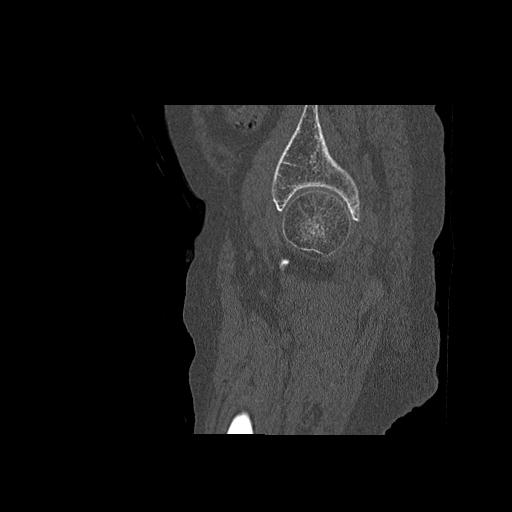

110286 2/17 股関節 2R 74歳女性 右人工骨頭